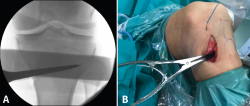

Figura 5. A: medición del ángulo de apertura de la osteotomía con el medidor; B: colocación del distractor en la parte posterior de la osteotomía, evitando así el aumento de la pendiente tibial posterior.

Posteriormente, bajo control radioscópico, se realiza la osteotomía apoyando la sierra por debajo de la aguja guía, llegando hasta 1 cm de la cortical lateral. Se introducen los escoplos para abrir la osteotomía (Figura 4). El primer escoplo, el más ancho, se introduce primero para comprobar el corte completo de la cortical posterior. Seguidamente, se coloca el medidor del ángulo de apertura (Figura 5A) y, a continuación, se introduce el distractor en la parte posterior de la osteotomía, evitando así un aumento de la PTP (Figura 5B). En este momento, se puede introducir en la apertura de la osteotomía el aloinjerto o sustituto óseo. Los autores utilizan aloinjerto óseo cuando la apertura es mayor de 10°. Antes de colocar y fijar la placa de osteotomía, se realiza el túnel tibial utilizando las herramientas artroscópicas clásicas (Figuras 6A y 6B). Al realizar una osteotomía biplanar, el corte es suficientemente distal como para permitir brocar el túnel tibial de la RLCA sin dificultades.